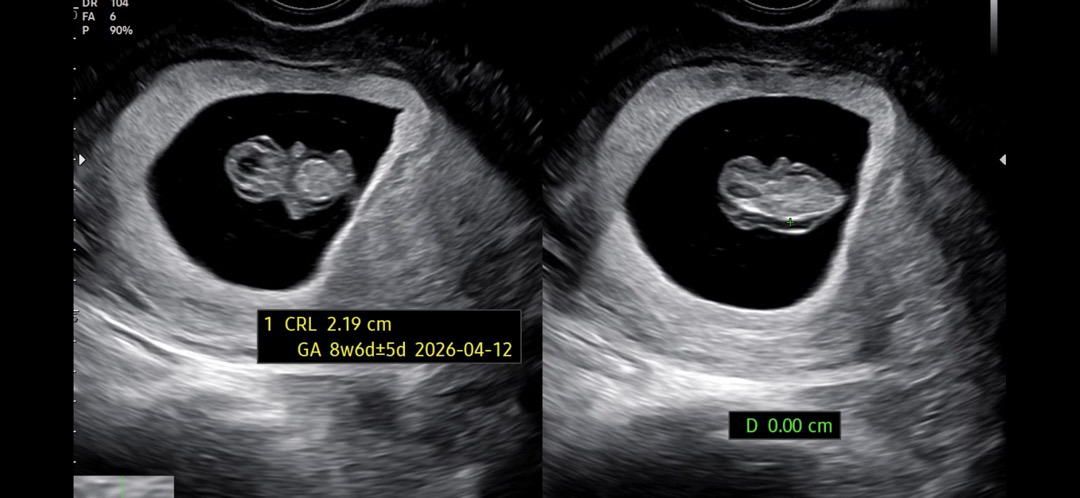

2주전 서브 a병원에 갔더니 선생님께서 말할까말까 고민하시다 아기가 부어있다고 말씀하시더라구요 이런경우 심장기형이나 림프관? 이 잘 못 형성되면 그럴 수 있다고. 그래서 일단 지켜보고 2주뒤에 니프티 검사 진행해보자고 하셔서 알겠다고 하고 걱정스러운 일주일을 보냈어요 그러고 딱 일주일 후 원래다니던 b병원으로 갔는데 배초음파로 봐서 그런지 저번주랑 다르게 피부가 떠있눈거 없이 너무 건강하게 잘 있더라구여ㅠㅠ 근데 배초음파로 봐서 약간 긴가민가한데 .. 선생님께 자초지종 설명드렸더니 자기는 태아가 부었다라는 말을 처음듣고 지금 애기 팔다리 다 생기고 건강하고 자궁도 깨끗하고 아기집크기도 좋고 괜찮다 2주뒤에 기형아검사하시면 된다라고 말씀해주시더라구요. 평소 조용하고 할 말만하시는 쌤인데 이렇게 말 많은 것도 첨보고 괜찮다 걱정말라는 말에 너무 큰 위안이되서 병원을 나왔어요 그런데 친구들에게 이러이러했다 이야기룰 하니 다들 또 다른 병원을 가봐라 거기서도 괜찮다는 소리를 들어야 마음이 놓이지 않겠냐 하면서 걱정해주더라구요..? 그래서 ... 아기가 부었다눈 말을 듣고 2주뒤가 이번주 토요일이거든요..? 다른 분들은 혹시 그 서브a병원을 가실지 아니면 대학병원을 갈지 아니면 그냥 아예 제 3의병원을 가야할지 ... 어떻게 하실 것 같으세요..? ㅠㅠ 난임병원다니면서 힘들게 얻은 아가라 .. 걱정도 많고 속상하내요ㅠㅠ 사진은 2주전 부었다고 했던 사진이에요